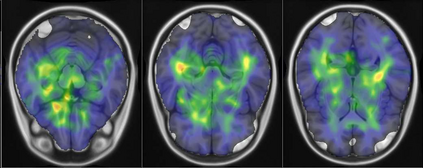

Representational similarity analysis (RSA) is a multivariate technique to investigate cortical representations of objects or constructs. While avoiding ill-posed matrix inversions that plague multivariate approaches in the presence of many outcome variables, it suffers from the confound arising from the non-orthogonality of the design matrix. Here, a partial correlation approach will be explored to adjust for this source of bias by partialling out this confound. A formal analysis will show the dependence of this confound on the temporal correlation model of the sequential observations, motivating a data-driven approach that avoids the problem of misspecification of this model. However, where the autocorrelation locally diverges from the volume average, bias may be difficult to control for exactly (local bias), given the difficulties of estimating the precise form of the confound at each voxel. Application to real data shows the effectiveness of the partial correlation approach, suggesting the impact of local bias to be minor. However, where the control for bias locally fails, possible spurious associations with the similarity matrix of the stimuli may emerge. This limitation may be intrinsic to RSA applied to non-orthogonal designs.